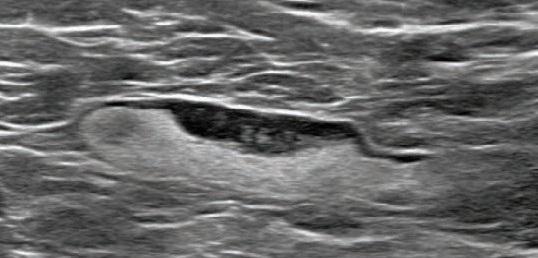

image: Screening mammogram and US demonstrated unilateral left axillary lymph node with cortical thickness of 5 mm on ultrasound (not shown). BI-RADS category 0 was assigned. Ultrasound from diagnostic work-up performed 7 days later showed no change in lymph node size. BI-RADS 3 was assigned.

Shabnam Mortazavi of the University of California at Los Angeles reviewed electronic medical records to identify women with post-COVID-19 vaccination adenopathy found from December 2020 to February 2021. For mammography, Mortazavi considered a node abnormal when its size, shape, or density was deemed disproportionate to other axillary nodes (ipsilateral or contralateral). On ultrasound, she deemed a node abnormal based on subjective assessment for cortical abnormalities, including focal or diffuse thickening greater than 3 mm, as well as nodal prominence compared to the contralateral axilla (when available). For MRI, Mortazavi considered a node abnormal when asymmetric in size and/or number to the contralateral axilla.

Twenty-three women exhibited axillary adenopathy ipsilateral to the vaccinated arm on screening or diagnostic breast imaging, and according to Mortazavi, "13% were symptomatic (axillary lump with possible tenderness)." Meanwhile, the adenopathy was detected incidentally on screening breast imaging in 43% (mammography, 5; ultrasound, 2; both mammography and ultrasound, 1; high-risk screening MRI, 2) and on diagnostic imaging for other reasons in 43% (BI-RADS 3 follow-up for breast finding, 3; screening callback for other reason, 2; non-axillary breast pain or lump, 5). Noting that the median interval between the first vaccine dose and imaging showing the abnormal node was 9.5 days, Mortazavi's results counted a total of 57% of women with one abnormal node. BI-RADS 2 was assigned in one woman, BI-RADS 3 in 21 (ultrasound in 4-24 weeks), and BI-RADS 4 in one.